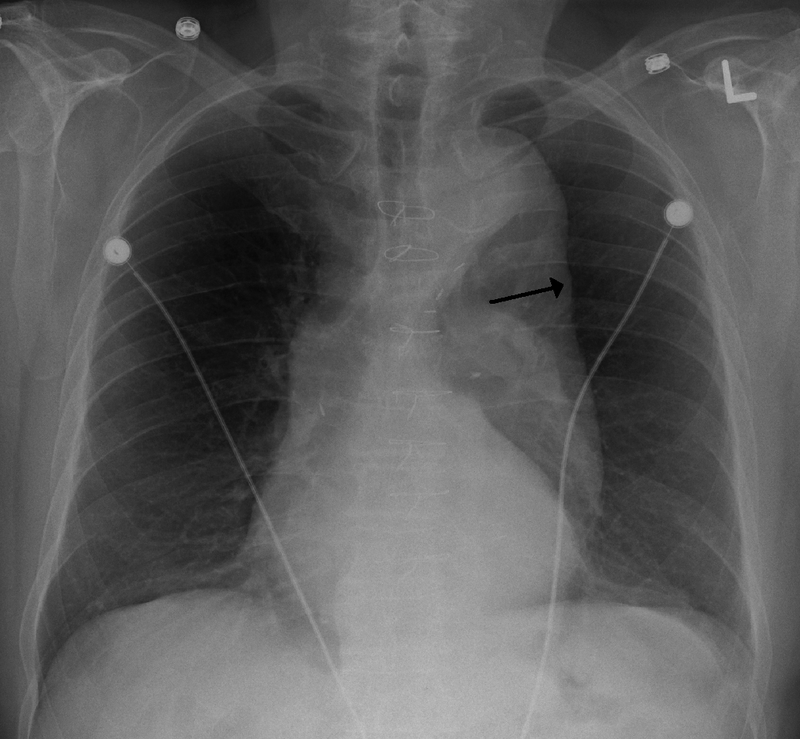

Abdominal Aortic Aneurysm

Abdominal aortic aneurysm (AAA) is an aneurysm of the abdominal aorta.

Abdominal aortic aneurysm typically develops above the aortic bifurcation but below the renal arteries.

Abdominal aortic aneurysm (AAA) is typically associated with hypertension and atherosclerosis.

Risk factors for abdominal aortic aneurysm (AAA) include:

- Male sex

- Smoking

- Elderly

- Atherosclerosis

- Hypertension

Atherosclerosis causes the vessel wall to atrophy and become weaker by raising the diffusion barrier to the media.

Abdominal aortic aneurysm (AAA) typically presents with a triad of:

- Flank pain

- Pulsating abdominal mass

- Hypotension

Symptoms of abdominal aortic aneurysm include an abdomen lump that pulses initially and enlarges over time.

Complications of abdominal aortic aneurysm (AAA) include:

- Rupture, especially when the diameter is greater than 5 cm

- Compression of nearby structures (such as the ureter)

- Thrombosis

- Embolism